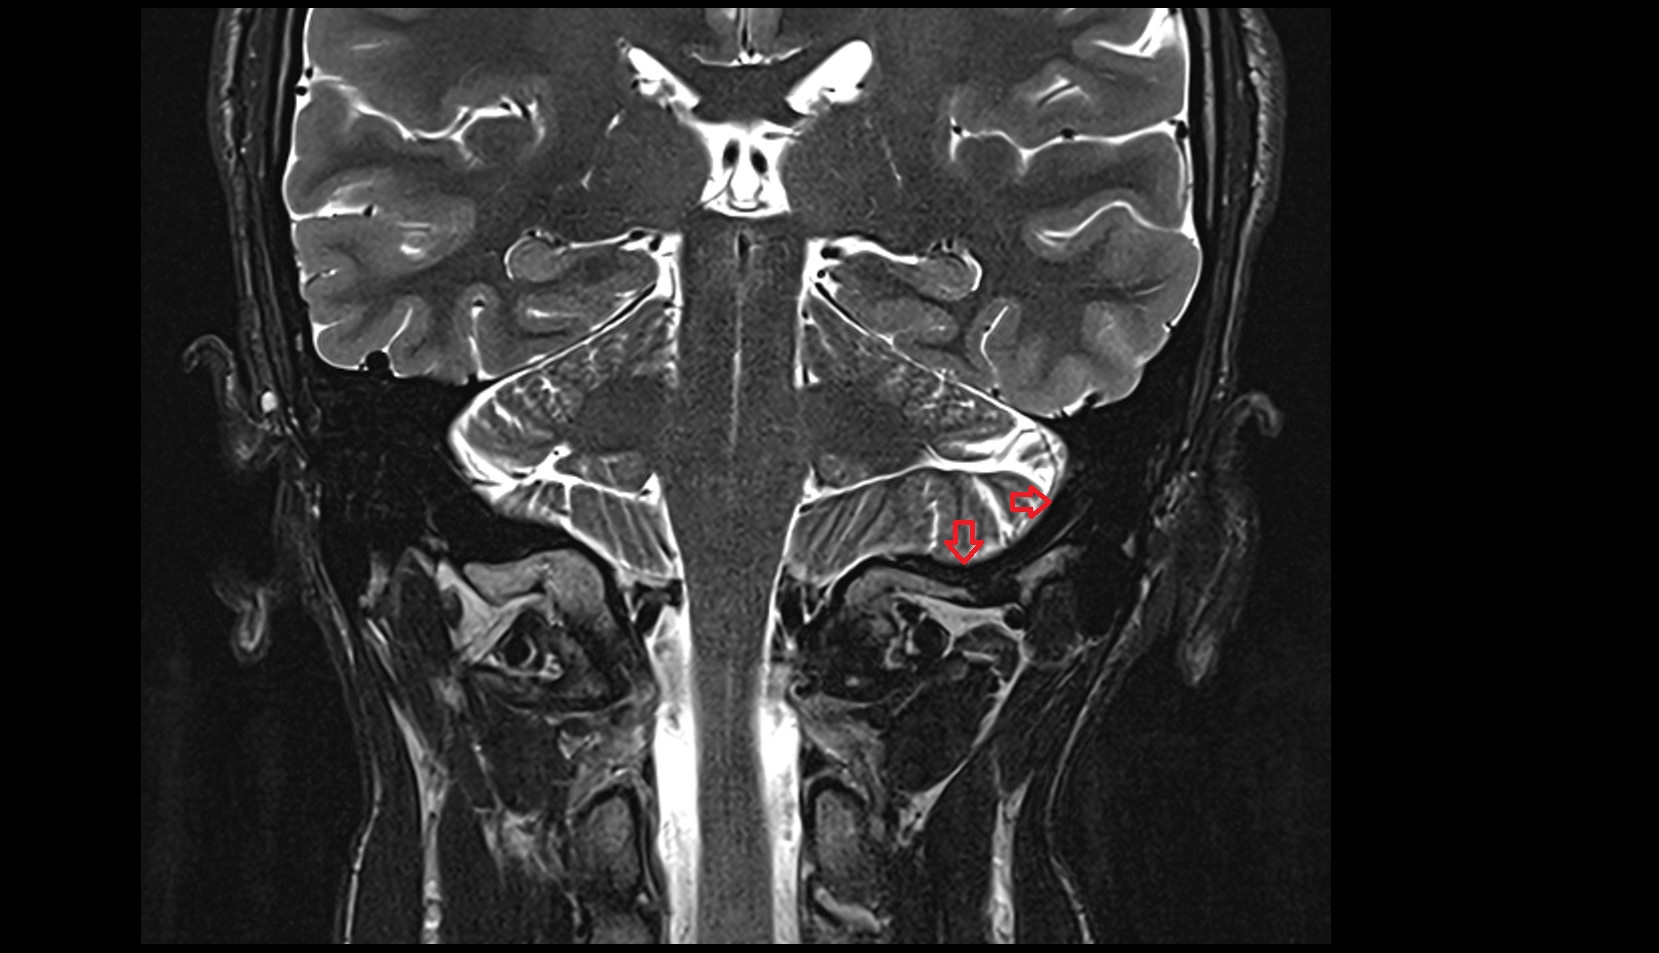

- Tonsil of cerebellum

- Cerebellar tonsil (H IX)